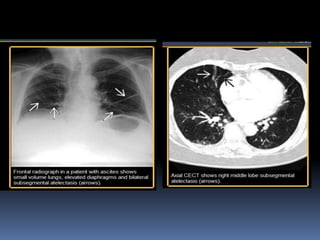

ATELECTASIA LINEAL

 RX y TAC . atelectasia lineal es un área focal.

 atelectasia con una configuración lineal, casi

siempre se extiende a la pleura.

 Es comúnmente horizontal pero a veces oblicua

o vertical.

 El espesor de la atelectasia puede variar desde

unos pocos milímetros a más de 1cm

 Atelectasia lineal es también llamado como

atelectasia discoide o forma de placa.

ATELECTASIA LINEAL  RXy TAC . atelectasia lineal es un área focal.  atelectasia con una configuración lineal, casi siempre se extiende a la pleura.  Es comúnmente horizontal pero a veces oblicua o vertical.  El espesor de la atelectasia puede variar desde unos pocos milímetros a más de 1cm  Atelectasia lineal es también llamado como atelectasia discoide o forma de placa.